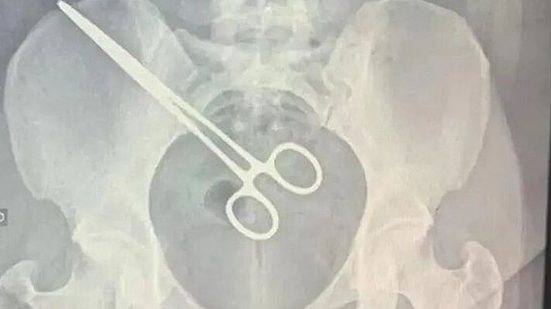

Uma pinça foi esquecida por pelo menos dois meses dentro de uma mulher que passou por uma cirurgia em Araçatuba (SP). A mulher foi submetida a um raio-x após tentar visitar o marido preso e foi constado metal em seu corpo.

O exame constatou a presença da pinça na região do útero dela, informou a TV Tem. A mulher fez uma cirurgia na Santa Casa de Araçatuba para retirada de um feto gerado em uma das trompas. A cirurgia ocorreu em setembro deste ano.

A Santa Casa de Araçatuba informou que a paciente passou por um procedimento para retirar a pinça. O órgão afirmou que iniciou uma apuração para esclarecer se a equipe médica seguiu os protocolos da casa e disse que "tomará as medidas necessárias de responsabilização ao final da apuração".